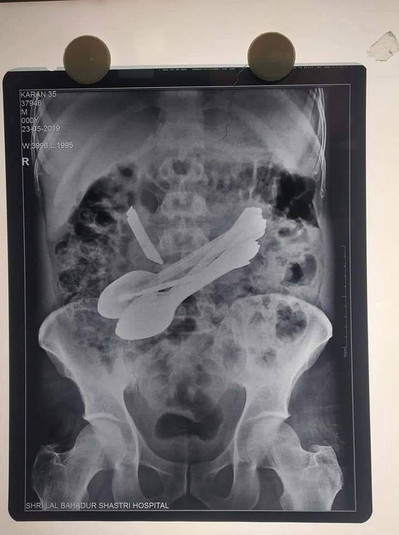

До індійським медикам звернувся чоловік з болями в животі, він був доставлений в урядовий медичний коледж Лал Бахадур Шастрі в районі Манді, Індія, де лікарі зробили рентген і виявили столові прилади всередині кишківника пацієнта і вирішили оперувати.

Під час процедури лікарі видалили сім маленьких сталевих ложечок, дві зубні щітки, дві маленькі викрутки, маленький ніж і стержень.